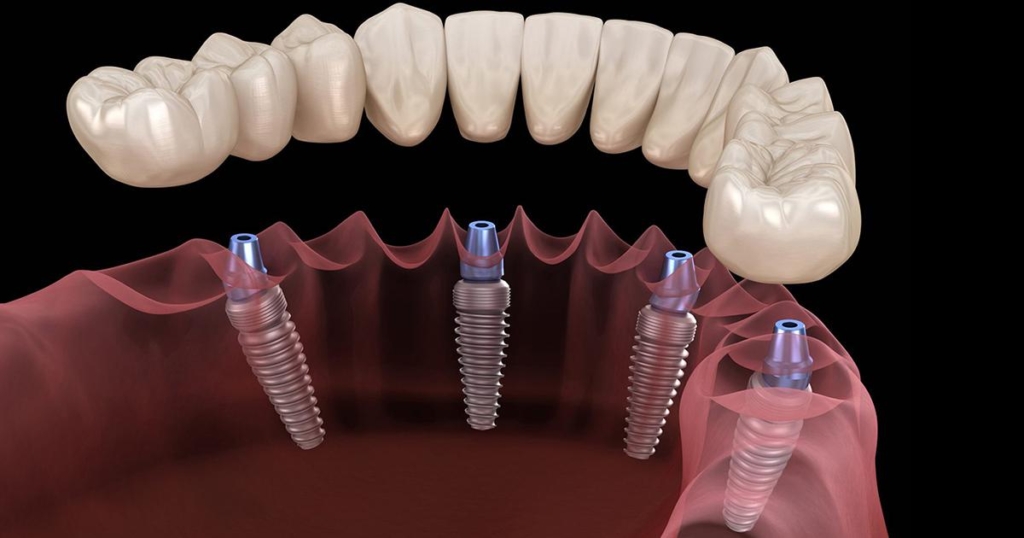

| RapidFixt 4 impianti tedeschi K3Pro + estrazione + 10-12 denti provvisori | 50000 lei |

| RapidFixt 6 impianti tedeschi K3Pro + estrazione + 10-12 denti provvisori | 70000 lei |